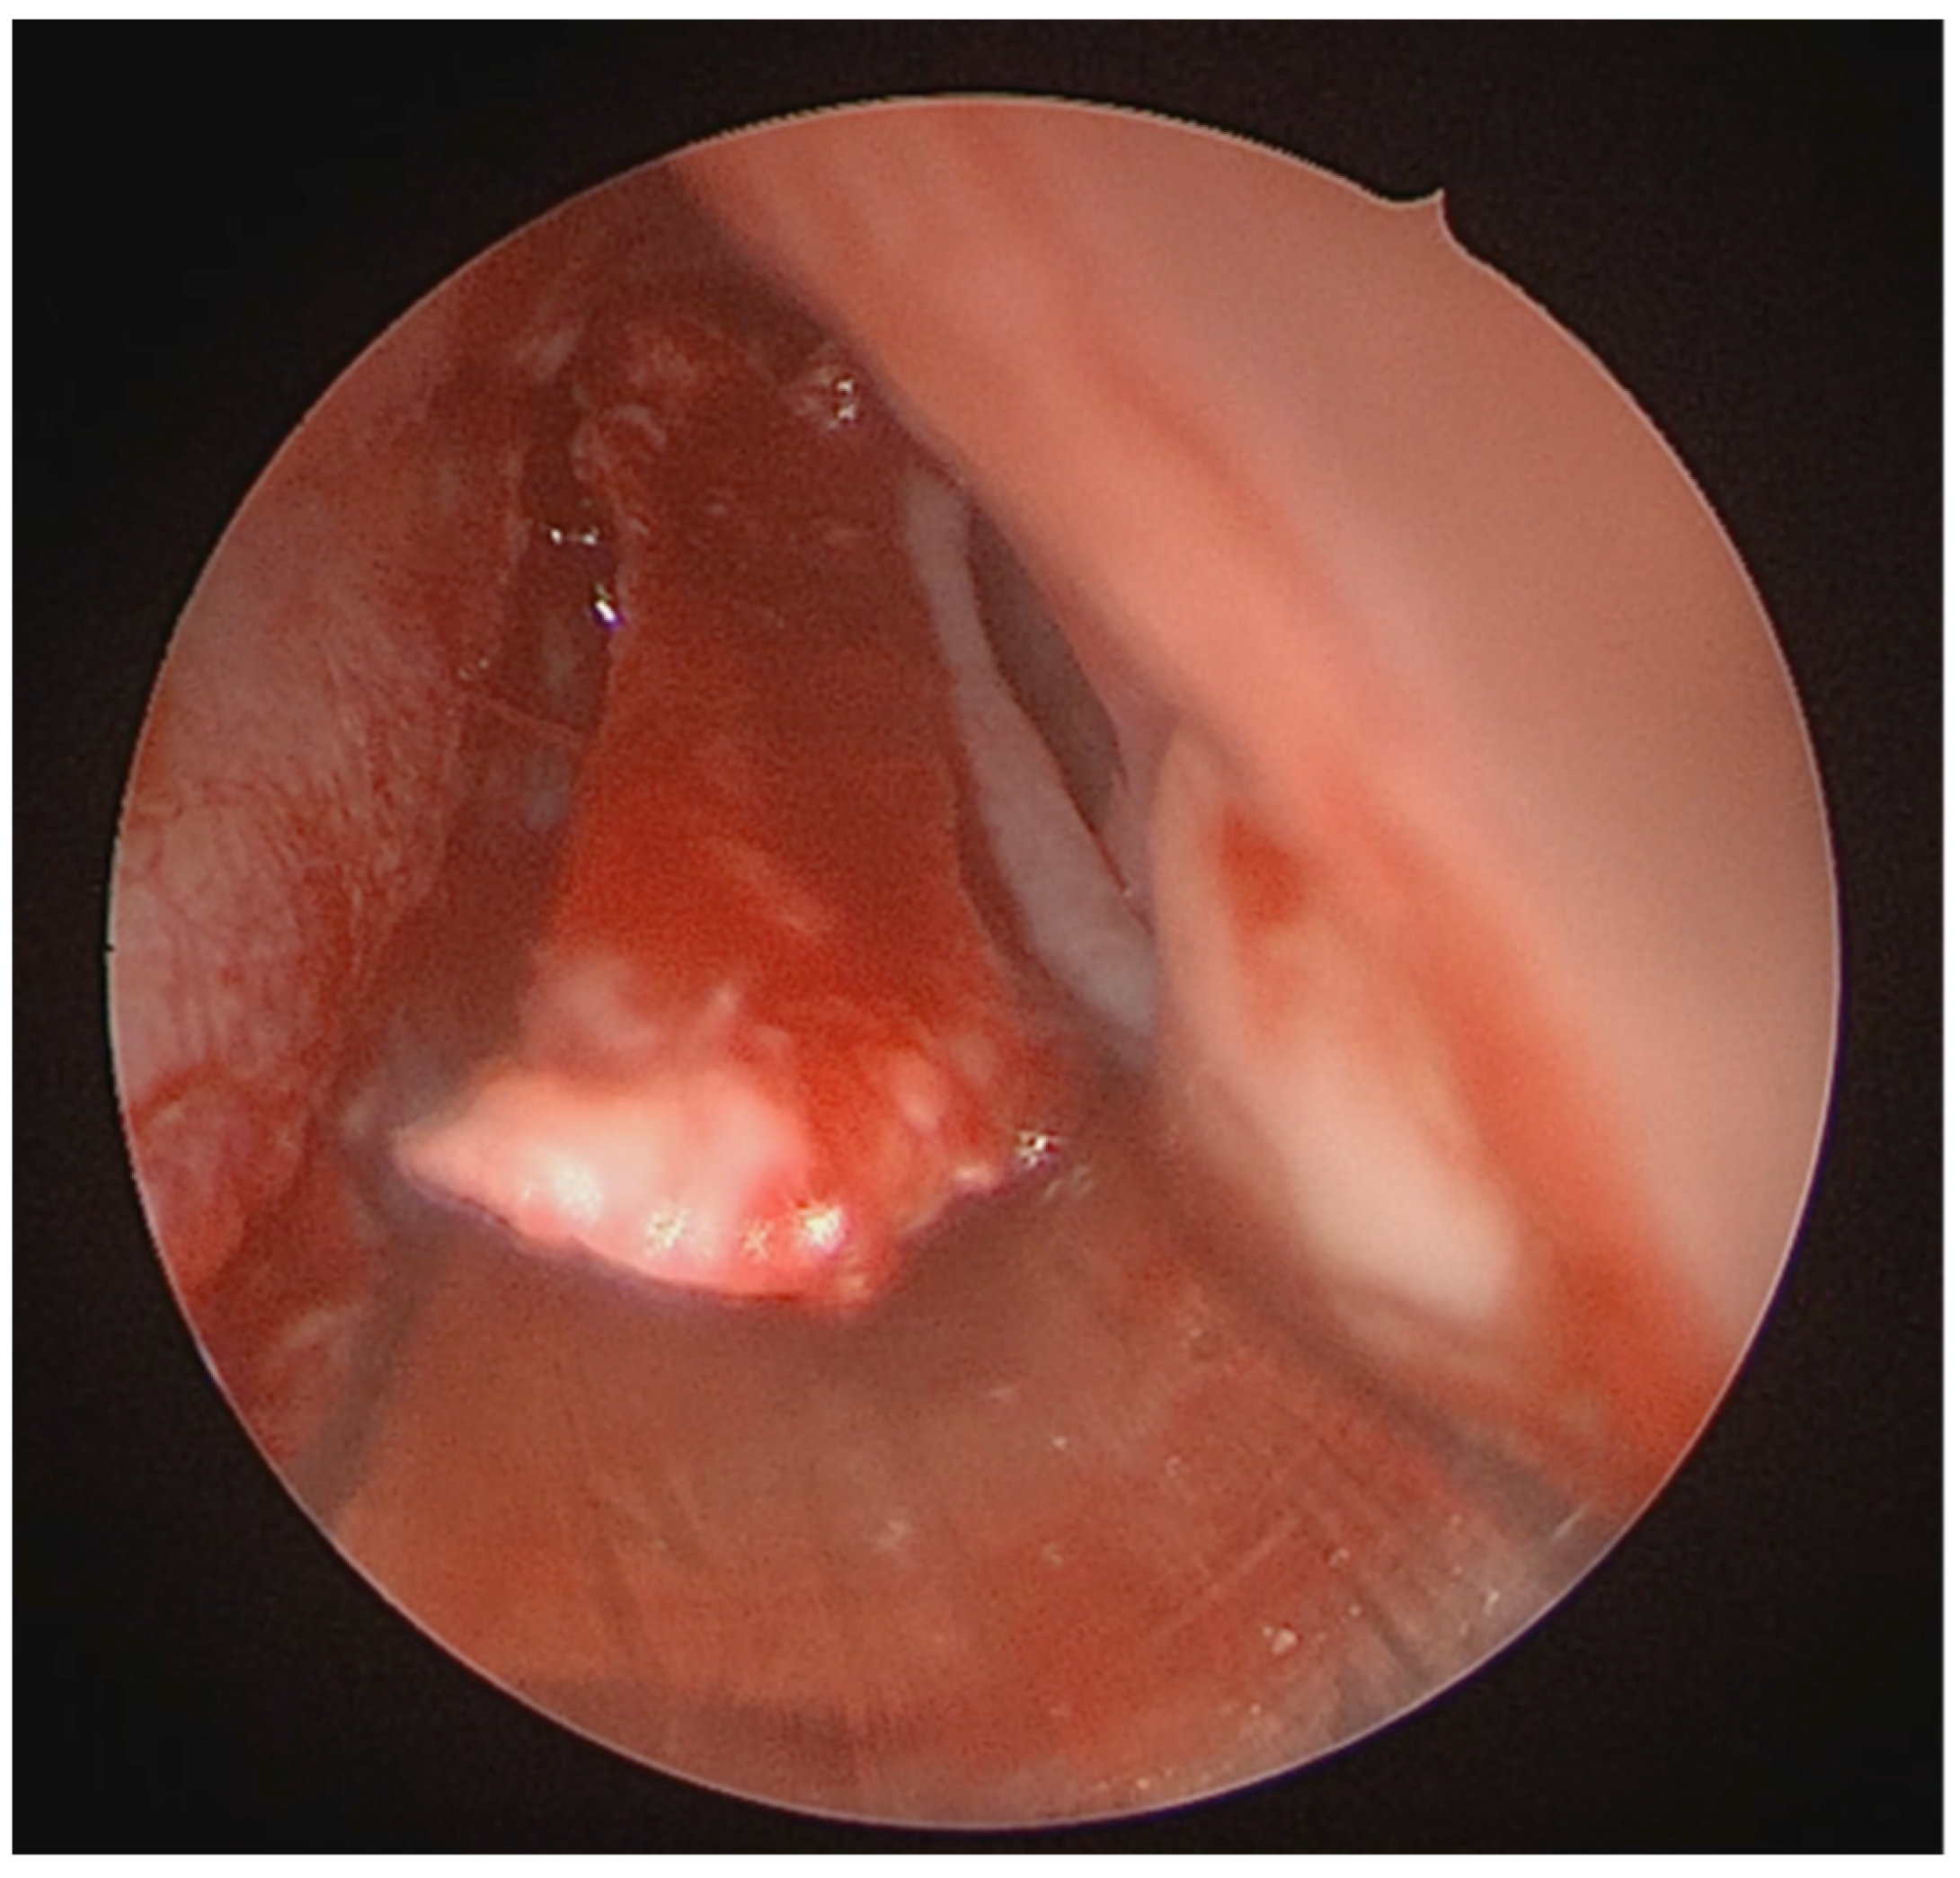

A full-thickness vertical incision was made through the cartilage a few millimeters anterior to the point of maximal deviation, which is typically located at the junction of the quadrangular cartilage and the perpendicular plate of the ethmoid [5]. The contralateral mucoperichondrial flap is then elevated in a similar manner. Once the cartilage and bone were separated from the mucosa, the deviated segments were excised using endoscopic instruments including forceps, Brünings punches, and scissors. The deviated portions of cartilage and bone were excised sharply, and the flaps are subsequently dissected inferiorly down to the nasal floor to correct deflections of the vomer. An osteotome was then positioned at the base of the spur to excise the bony protrusion (Figure 3). Deviated bony segments from the vomer or perpendicular plate of the ethmoid were removed as needed (Figure 4). After complete removal of the spur, the mucoperichondrial flaps were restored to their native positions [15]. When flap apposition was satisfactory, suturing was not required; in such cases, the incision line could be covered with a small segment of Gelfilm. Nasal packing and splints were employed only in selected cases [4].

Figure 4. Resection of the deviated nasal spur using Bruenings septal forceps.